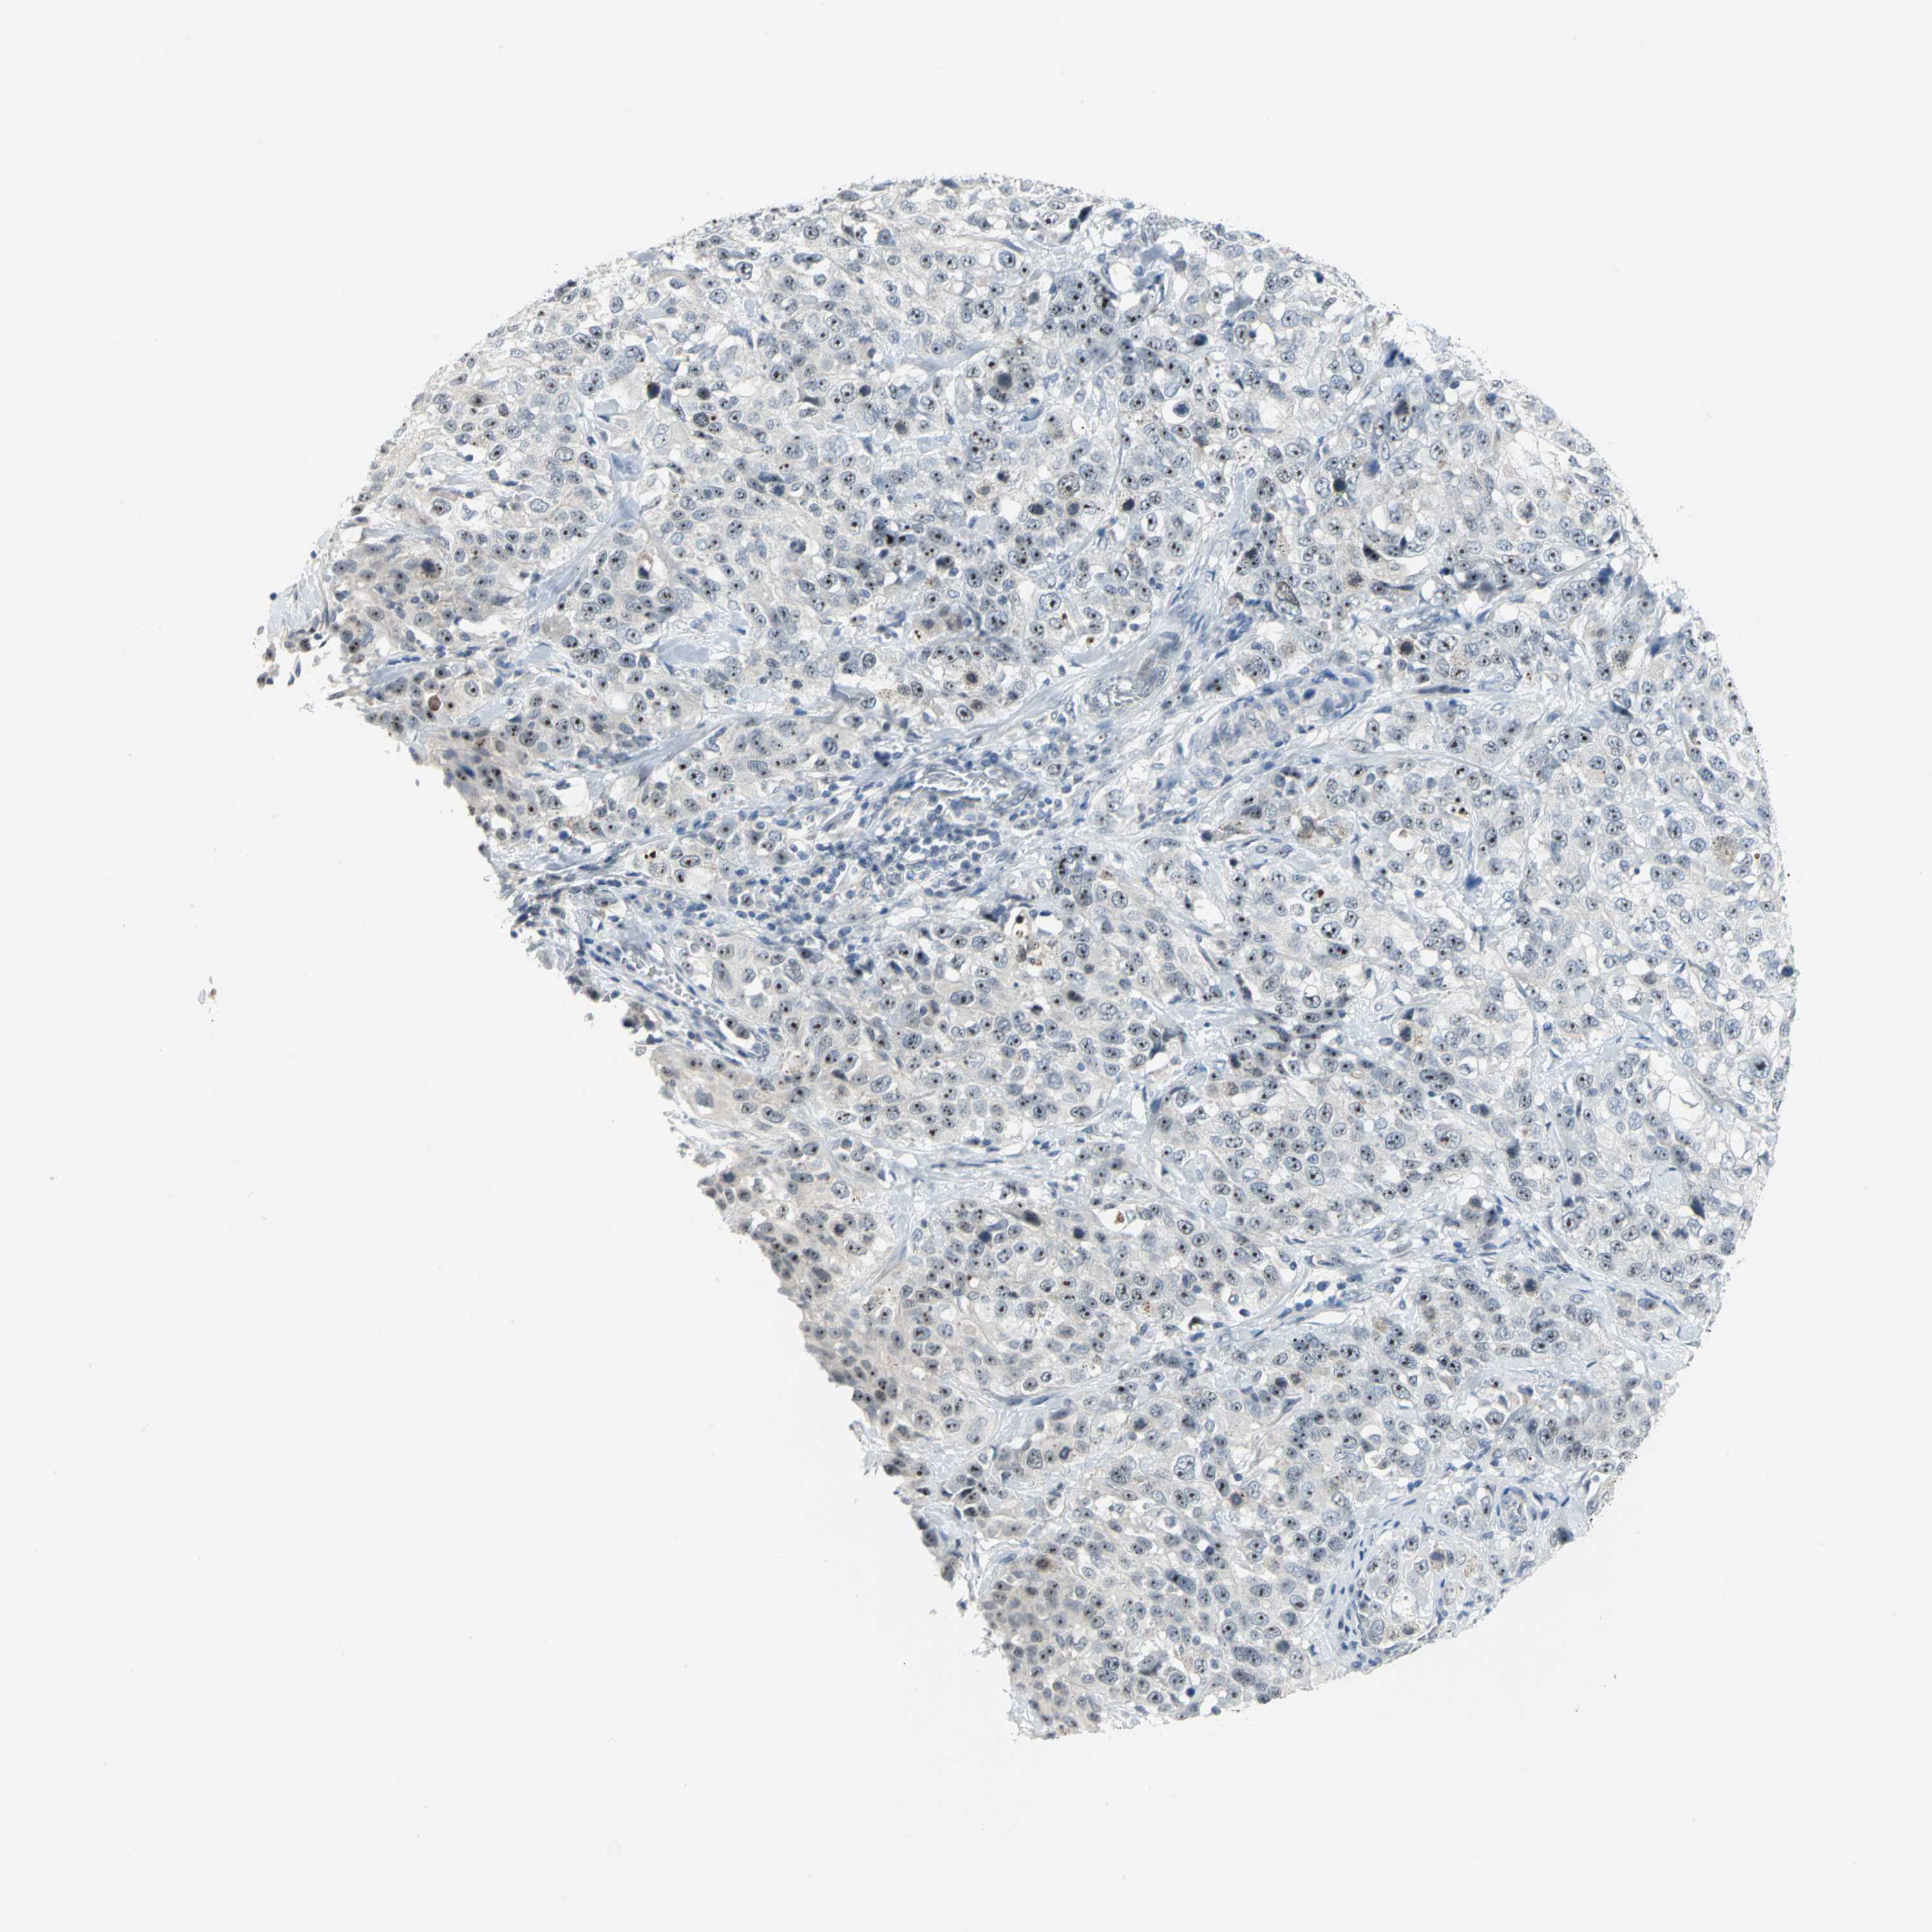

STOMACH CANCER - Protein expressioni

A mouse-over function shows sample information and annotation data. Click on an image to view it in a full screen mode. Samples can be filtered based on level of antibody staining by selecting one or several of the following categories: high, medium, low and not detected. The assay and annotation is described here.

Antibody stainingi

Antibody staining in the annotated cell types in the current human tissue is reported as not detected, low, medium, or high, based on conventional immunohistochemistry profiling in selected tissues. This score is based on the combination of the staining intensity and fraction of stained cells.

Each image is clickable and will lead to virtual microscopy that enables deeper exploration of all samples and also displays staining intensity scores, fraction scores and subcellular localization as well as patient and tissue information for each sample.

Antibody HPA005466

Staining

High

Medium

Low

Not detected

Intensity

Strong

Moderate

Weak

Negative

Quantity

>75%

75%-25%

<25%

None

Location

Nuclear

Cytoplasmic/membranous

Cytoplasmic/membranous,nuclear

Adenocarcinoma, NOS